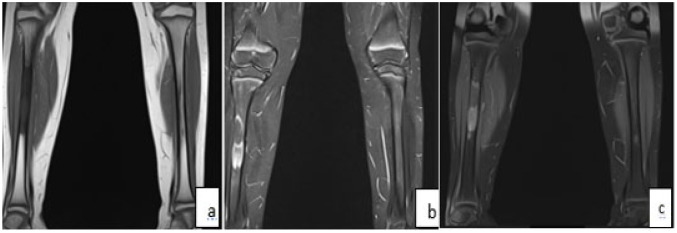

纤维发育不良是一种罕见的非遗传性先天性疾病,主要有两种形式:单相和多相。单恒定型较为常见,而多恒定型通常伴有综合征,较为罕见。本病例涉及一名 10 岁的患者,他被诊断为多发性纤维发育不良并伴有内分泌病。本报告根据患者的病例,从临床和放射学方面探讨了这种疾病。

Fibrous dysplasia is a rare non-hereditary congenital condition characterized by 2 main forms: monostotic and polyostotic. Monostotic is the more common form, while polyostotic, often associated with a syndrome, is rarer. The case presented involves a 10-year-old patient who was diagnosed with polyostotic fibrous dysplasia accompanied by an endocrinopathy. This report explores the clinical and radiological aspects of this condition based on the patient's case.